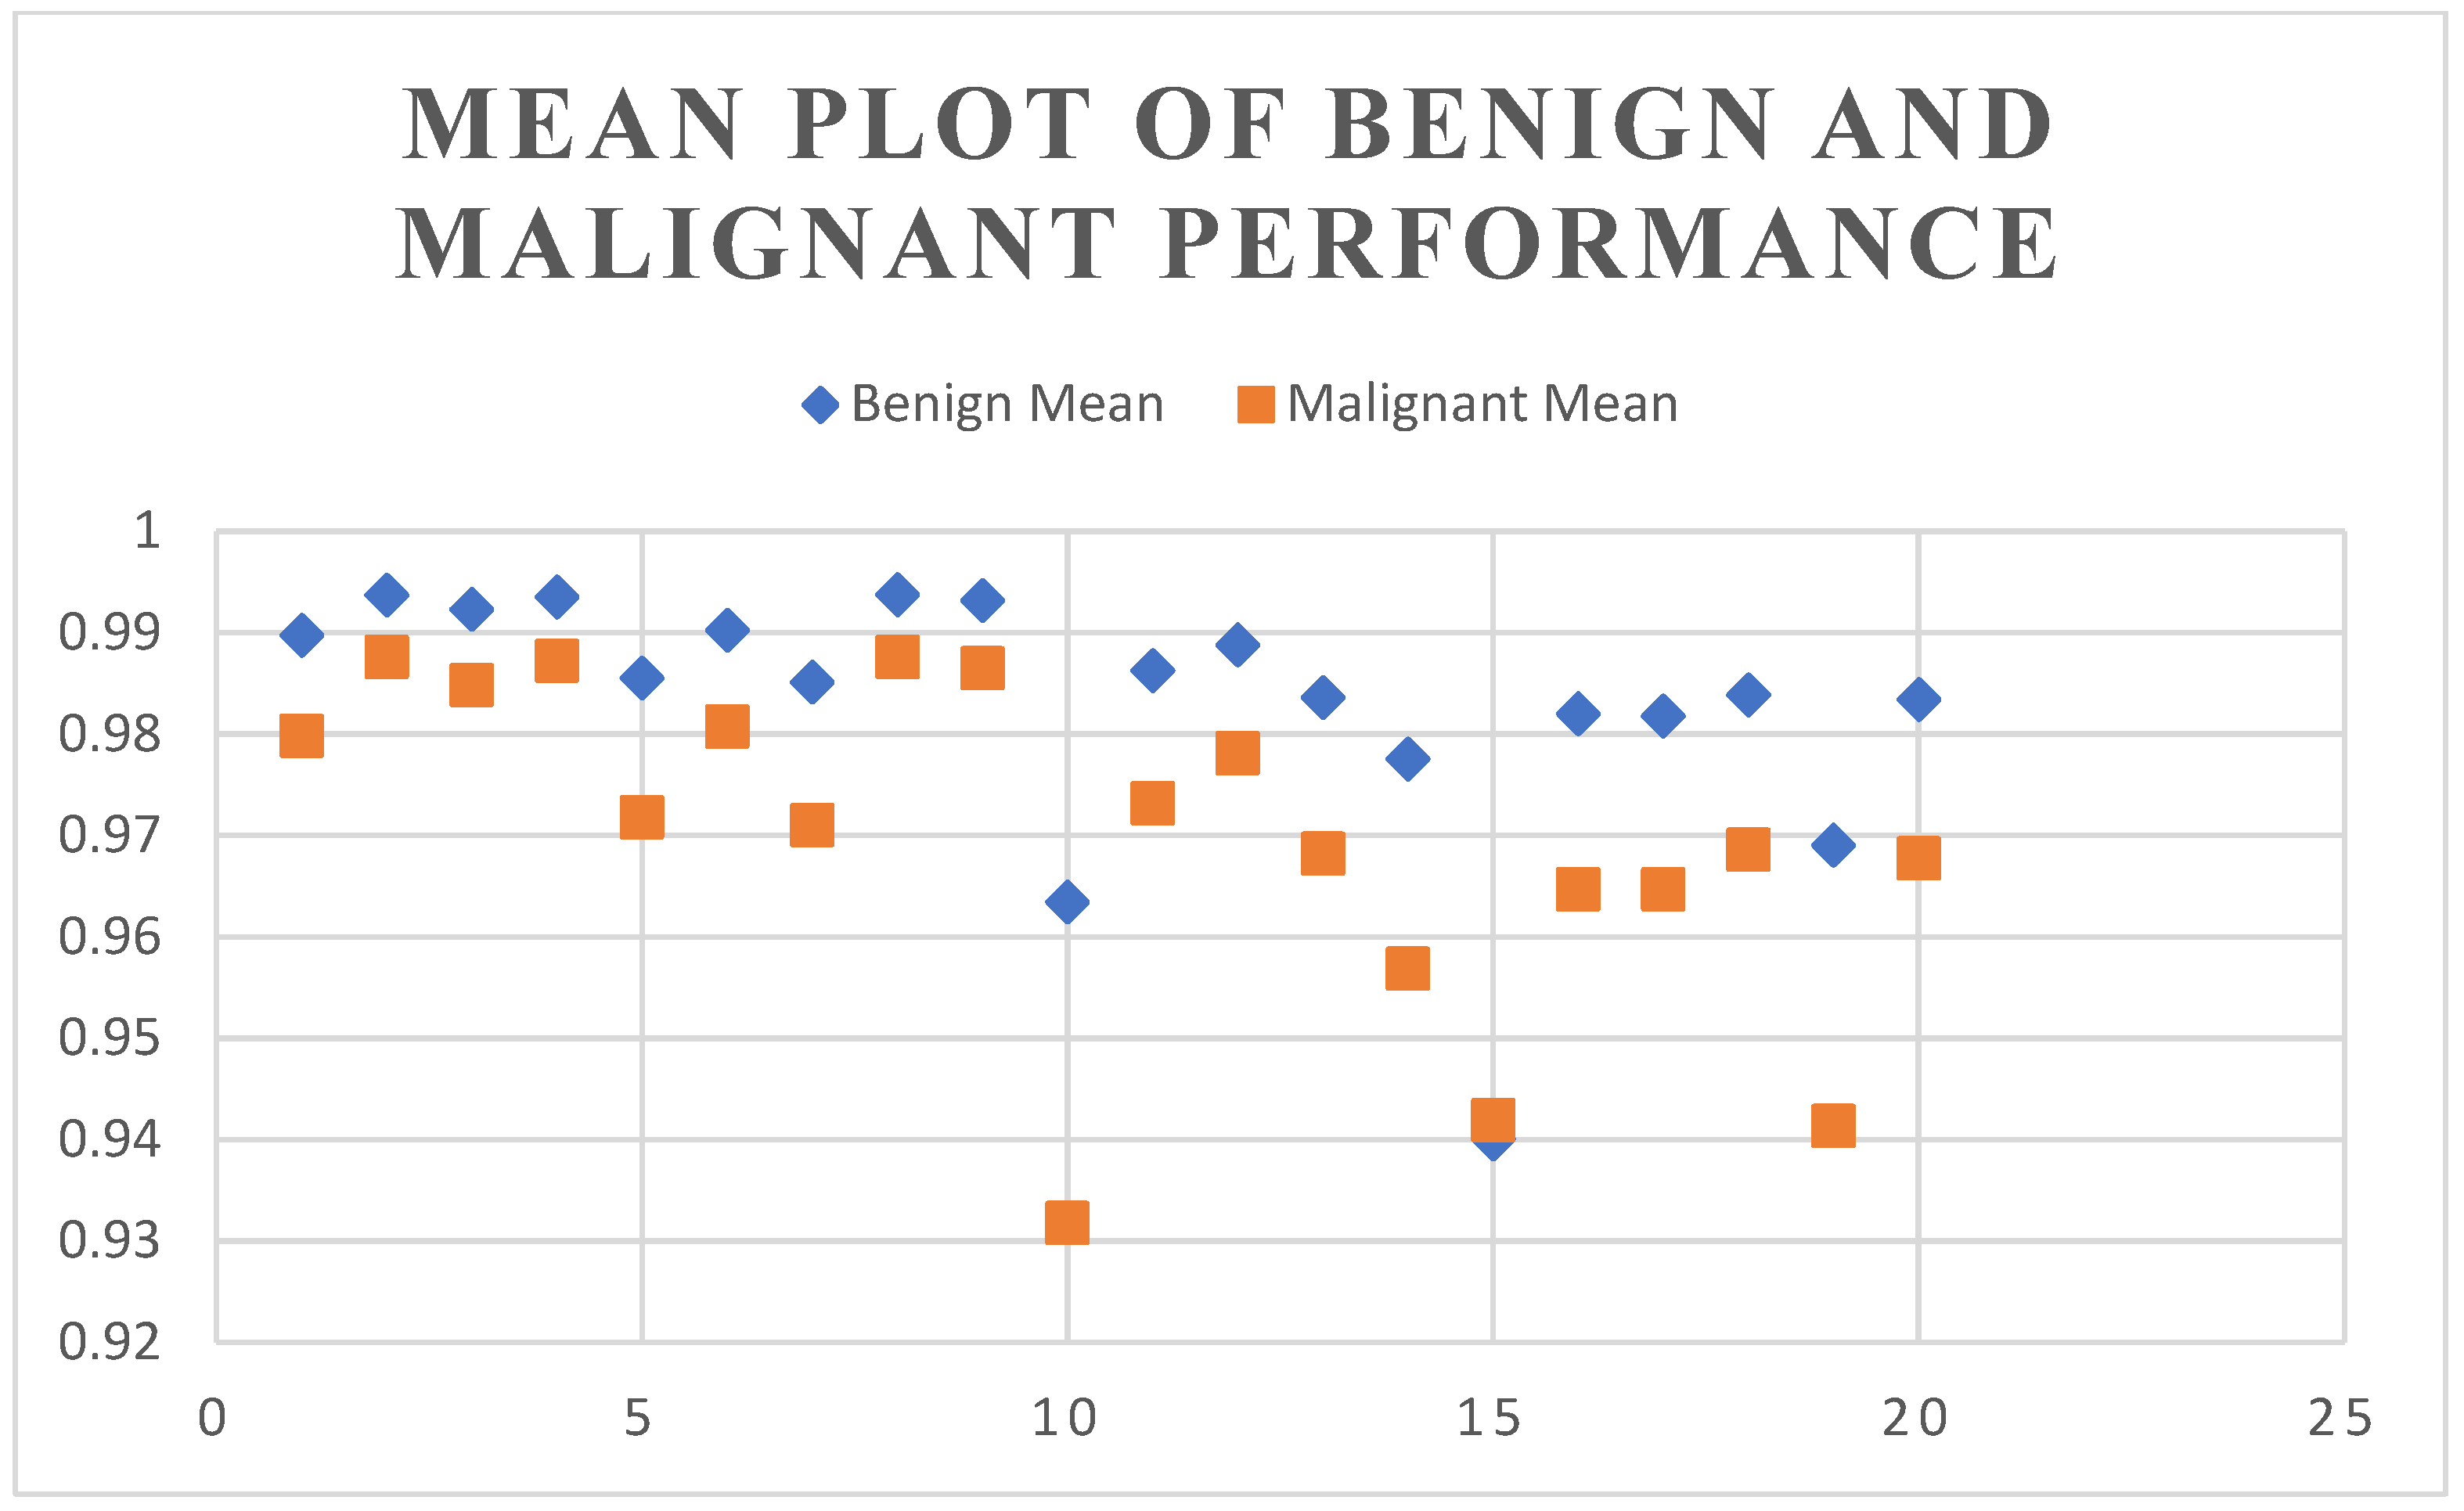

4.2. Segmentation Results Using the UNet Model